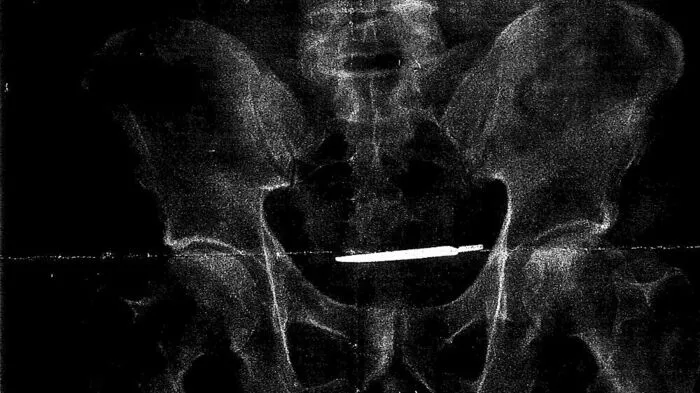

Skalpell bei Operation im Körper vergessen

Das Röntgenbild zeigt ein Skalpell, das offenbar im Körper des US-Amerikaners Glenford Turner bei einer Operation im Jahr 2013 vergessen wurde.